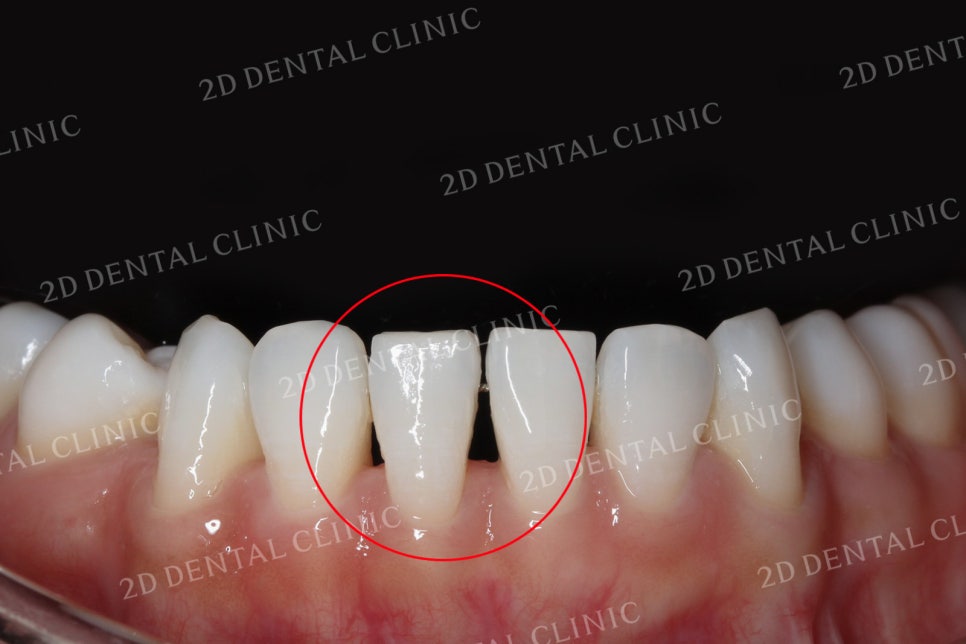

치아틈새를 완벽하게 메꾸는 방법, 치간이개로 인한 블랙트라이앵글을 쎄라필름(TheraFilm)으로 완전히 삭제하기! 입니다. 오늘 소개해드릴 Case의 환자분께서는 치아 사이의 틈! 치간이개로 인한 블랙트라이앵글이 심각한 상태로 진행되신 상태였습니다. 이러한 블랙트라이앵글은 나이가 들면서 서서히 약해지는 구강 내 지반, 잇몸, 잇몸 뼈들이 퇴축함으로써 자주 발생하게 됩니다. 이에 따라 잇몸이 내려 앉고 치아의 뿌리가 드러나면서 시리고 통증을 유발하게 됩니다. 아래의 사진을 보시면서 자세한 설명을 이어가겠습니다.

쎄라필름 시술 전

환자분의 쎄라필름 시술 전 치아 사진입니다.

치아의 상태를 보시면 중간 중간 치아 사이의 틈새가 까맣게 보이는 것을 확인하실 수 있습니다.

치아의 뿌리가 드러나게 되면 잇몸이 치아를 지탱하는 힘이 약해짐은 물론이며,

시린이, 풍치 등 여러 구강질환을 유발할 수 있습니다.

전치부의 자세한 사진을 보시면 치아의 절단연 부분이 고르지 못하고

울퉁불퉁한 모습을 보실 수 있습니다.

교합 시 하악의 중절치 부근에 블랙트라이앵글이 심하게 발생한 모습입니다.

상악 역시 중절치의 치간이개가 많이 진행된 모습이네요.

구강 개방 시 치아의 사진입니다.

표시된 부분에서 블랙트라이앵글이

확실하게 관찰되고 있네요.

이번 환자분께서는

상악 전치부의 6개 치아와

하악 전치부 6개 치아,

총 12개의 치아에 쎄라필름

시술을 진행하셨습니다.